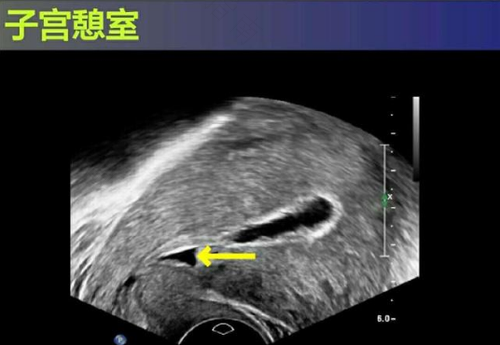

子宫瘢痕憩室的意思,就是子宫下段切口处形成了一个与宫腔想通的凹陷或憩室,子宫瘢痕憩室一般会引发女性出现一些症状,而且这些正常的轻重程度和憩室大小有一定的关系,如果憩室比较小的话,那么一般不会引起什么明显症状。

如果子宫瘢痕憩室比较大,那么经血引流就会受阻,导致经血淤积在憩室内,从而引起经期延长、经期淋漓不尽等现象,这也是子宫瘢痕憩室比较常见的症状。子宫瘢痕憩室常发生在剖腹产的女性身上,而且出现这种情况的几率越来越高。